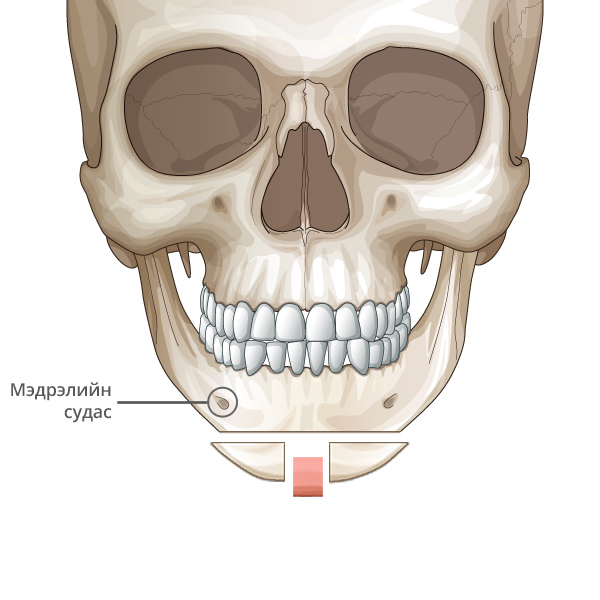

Мэдрэлийн судаснаас зайлсхийж, эрүүний төгсгөлд зүсэлт хийнэ.

Ясны гол хэсгээс тайралт хийж авна.

Зүсэлт хийгдсэн эрүүний хоёр талыг нийлүүлнэ.

Эрүүний ясыг нийлүүлж тогтоож өгнө.

Хоёр хажуу талд товойж харагдах ясны хэсгийг тайрна.